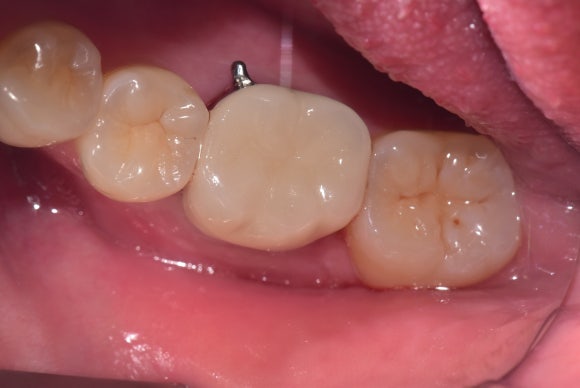

20250228

다행히 호전이 빠르셔서

2개월만에 치료를 종료할 수 있었습니다.

신경치료된 어금니는 평생 입 안에서

맞은편 치아, 음식 등과 부딪히며 살아야 합니다.

튼튼한 크라운으로 머리를 보호해줍니다.